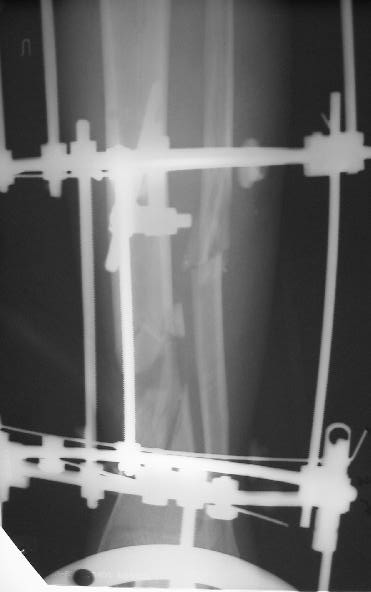

Больному 7 дней назад плита придавила голень стопу. Диагноз Открытый ( 3 б по Каплану) сложный многооскольчатый перелом с выраженным раздроблением н/3 диафиза голени, перелом лодыжек без смещения, перелом основания 5 плюсневой кости с небольшим смещением.

По моему мнению во-первых нужно гешить проблему мягких тканей, для этого провести вторичную и третичную и сколько понадобится обработок при этом удаляя все свободные и инфицированные костные фрагменты - безжалостно и после этого надежное закрытие кожного дефекта с запасом, лучше всего микрохирургический соседистый лоскут . Когда мягкие теани будут готовы в зависимости от размера дефекта можно решить что делать. Лично я предпочитаю замещение дефекта по Илизарову в классическом варианте - остеотомия проксимального отдела тибии и дистальное перемещением с формированием регенерата. Тем более аппарат уже есть. Я бы не стал фиксировать стопу. Судя по снимку дистальный фрагмент достаточно большой, но посмотрим что останется после последней ХО.

А где дефект? Толком не видно.

Согласен с коллегами , что фиксация стопы тут избыточна, и что дефекта не видно.

Больного прооперировал, обработку мягких тканей на голени не стал делать, думаю, некроз по краю швов на голени заживет под струпом (рис 3). На стопе удалил некротические ткани, готовлю ее к аутопластике (рис 2).

На дополнительных снимках итраоперационно видна значительная потеря массы (рис 6 рис 1). Хотя на снимках контрольных после операции вроде дефекта значительного нет. Все же придется, как-то замещать дефект костный на голени, думаю подготовить морально больного к повторной операции костной пластике, после заживления ран.